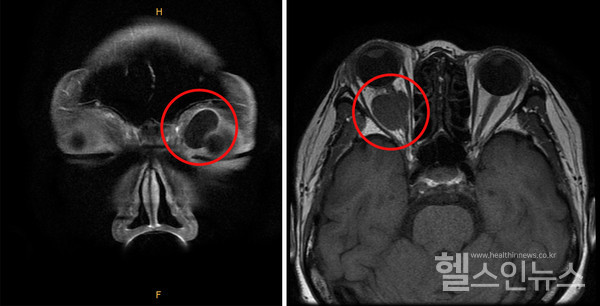

(좌측)좌측안와앞쪽에생긴낭성종괴,(우측)우측안와뒤쪽에생긴시신경종양

안와 양성 종양은 일반적으로 수술을 통해 제거할 수 있으나, 발생 위치에 따라 합병증 발생 위험이 있을 수 있으므로 신중하게 치료 방향을 결정해야 한다. 먼저 수술 전 CT 및 MRI 검사를 통해 종양의 크기, 위치, 성상을 정확하게 파악하고 분석한다. 안와 앞쪽에 위치한 종양은 상대적으로 쉽게 제거할 수 있다. 흉터 없이 제거하기 위해 쌍꺼풀 라인을 따라 절개하고 수술을 진행하기도 한다.

안와 뒤쪽에 위치한 종양도 종류에 따라 박리가 비교적 쉬운 종양도 있으나, 일부는 합병증 발생 위험이 있다. 특히 안구 뒤쪽으로 시신경이 뇌와 연결되는 구멍이 있는 ‘안와첨’은 좁은 공간 내 많은 신경과 혈관, 외안근 시작 부위 등이 가깝게 자리 잡고 있어, 종양 수술 후 합병증 발생 위험이 높아 수술 여부를 신중하게 검토해야 한다. 이에 안와첨 종양은 수술이 아닌 사이버나이프 같은 방사선치료를 통해 크기를 줄이는 치료를 시행하기도 한다.

안와 뒤쪽 공간에 종양이 발생하면, 종양의 크기가 꽤 커질 때까지 환자가 증상을 느끼지 못하는 경우가 많다. 시력이나 시야에 이상이 없고, 안구 움직임에도 영향을 주지 않는 양성종양의 경우 경과 관찰을 하는 것으로 치료 방향을 결정하기도 한다.